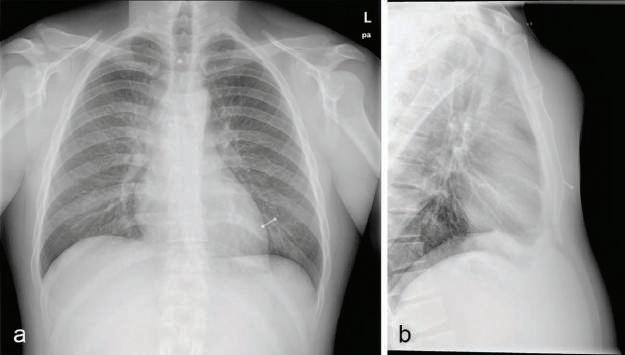

Fig.2.6 (A)Preoperativesagittalcomputedtomographyofchestrevealingaposteriordislocationofthe sternalbodyonthemanubrium.(B)Preoperativesagittalthree-dimensionalreconstructionofchest. (C)Postoperativechestroentgenogramwithsternalfixationplatesandscrews (blue).(D)Postoperative lateralchestroentgenogramrevealingstablesternumwithfixationplateandscrews.(FromSarkeshik AA,JamalA,PerryPA.Manubriosternaljointdislocationduetobluntforcetrauma. TraumaCaseRep 2019;21:100187[Fig.1].ISSN2352-6440, https://doi.org/10.1016/j.tcr.2019.100187, http://www. sciencedirect.com/science/article/pii/S2352644019300214.)

collagenvasculardiseaseisindicatedin patientssufferingfrommanubriosternaljointpainifotherjointsareinvolv ed.Magneticresonanceimaging(MRI), ultrasoundimaging,and/orcomputed tomography(CT)ofthejointisindicatedifjointinstability,infection,oroccultmassissuspected,ortofurtherelucidatethecauseofthepain(Figs.2.10 and 2.11 ).TheuseofmultidetectorCT forpatientspresentingtotheemergencydepartmentwithacutechestpainhas ledtomorerapidandaccuratediagnosi sofchestwallpainsyndromes(see Fig.2.6 ).Theinjectiontechniquedescribed laterservesasbothadiagnosticand atherapeuticmaneuver(Fig.2.12 ).

Asmentioned,thepainofmanubriosternalsyndromeisoftenmistakenforpain ofcardiacorigin,anditleadstovisitstotheemergencydepartmentandunnecessarycardiacworkups.Iftraumahasoccurred,manubriosternalsyndromemay coexistwithfracturedribsorfracturesofthesternumitself,whichcanbemissed onplainradiographsandmayrequireradionuclidebonescanningforproper identification.Tietzesyndrome,whichispainfulenlargementoftheuppercostochondralcartilageassociatedwithviralinfection,maybeconfusedwithmanubriosternalsyndrome.